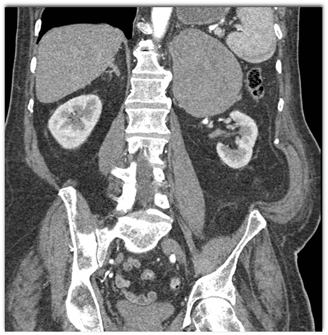

The most likely diagnosis in this case is

adrenal adenoma

pheochromocytoma

lymphoma

metastatic melanoma